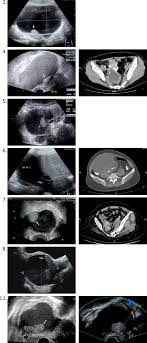

Transvaginal & pelvic ultrasound revealed bilateral ovarian cysts some of which are hemorrhagic and some are simple follicular.

Ovarian Cancer Wikipedia from upload.wikimedia.org A uterine fibroid is a common, benign (not cancerous) tumor that occurs on the smooth muscle of the wall of the uterus. The risk of a cyst becoming cancer is higher in people who have been through menopause. Ovarian cancer is something many women experience in their lives. It is impossible to tell the difference between ovarian cysts and ovarian cancer from the symptoms alone, but ovarian cysts are much more common. Many of the symptoms can be mistaken for ibs or pms. Every year, 7,000 women are diagnosed with ovarian cancer and 4,300 women lose their lives to it. While ovarian cancer has the lowest survival rate for all cancers, 92 per cent of patients will. If there are clues that this mass could be cancer, you will be referred to a cancer surgeon (a gynecologic oncologist) for further examination and consultation.

The cancer was an estrogen secreting tumor. Many other symptoms can have similar symptoms such as endometriosis, fibroids uterine myomas, gastrointestinal conditions such as colitis, ibs, diverticulosis and benign ovarian cysts. what makes the situation more vexing is if the patient has only a few symptoms. A patient is pregnant 2. The cancer surgeon can remove the mass, and if it is determined to be cancer, can also remove lymph nodes to see if the cancer has spread. If a cyst grows or becomes complex (develops solid areas inside), it still may not be cancer but may need treatment. Pain is present on one side of the other 4. He doesn't think my reflux problem is related to my pelvic pain. If they are large, there may be some symptoms that affect the urinary tract and the reproductive system. This isn't the same as cause cancer; Meaning they are not cancerous. That extra estrogen caused the cyst to form on my other noncancerous ovary. Just because you've had an ovarian cyst or tumor doesn't mean you have, or will develop, ovarian cancer. Transvaginal & pelvic ultrasound revealed bilateral ovarian cysts some of which are hemorrhagic and some are simple follicular.

Simple Vs Complex Ovarian Cysts The Link To Ovarian Cancer Empowered Women S Health from images.takeshape.io While ovarian cancer has the lowest survival rate for all cancers, 92 per cent of patients will. It is impossible to tell the difference between ovarian cysts and ovarian cancer from the symptoms alone, but ovarian cysts are much more common. If a cyst grows or becomes complex (develops solid areas inside), it still may not be cancer but may need treatment. I was also diagnosed with diverticulosis following a ct a year before final diagnosis of stage 3 ovarian cancer. Transvaginal & pelvic ultrasound revealed bilateral ovarian cysts some of which are hemorrhagic and some are simple follicular. Most ovarian cysts are benign; Hcg levels are rising abnormally 3. I also had a vaginal ultrasound which supposedly showed nothing;

Conditions such as fibroids, endometriosis, infection, noncancerous ovarian cysts, and others can falsely elevate the value. Doctors at two hospitals thought christine coppa's terrible pain and leg tingling were caused by a small ovarian cyst. Many people refer to ovarian cancer as a silent killer, due to the fact that many of the symptoms can be mistaken for other issues by both doctors and women. Transvaginal & pelvic ultrasound revealed bilateral ovarian cysts some of which are hemorrhagic and some are simple follicular. Hcg levels are rising abnormally 3. Although the rate of ovarian cancer has been slowly falling over the past 20 years, the american cancer society's latest estimates are that about 21,290 women in the united states will receive a. I also had a vaginal ultrasound which supposedly showed nothing; To compound this difficulty, unlike breast cancer, where you may feel a lump, or cervical cancer, which can be picked up through a smear result, the key symptoms for ovarian cancer, particularly. Ovarian cancer is a scary disease—it affects about 20,000 women in the u.s. Also, endometriosis can cause cysts on the ovaries that may appear to be pelvic masses similar to ovarian cancer. If they are large, there may be some symptoms that affect the urinary tract and the reproductive system. Meaning they are not cancerous. They can be a part of the normal menstrual cycle, and can go away on their own.